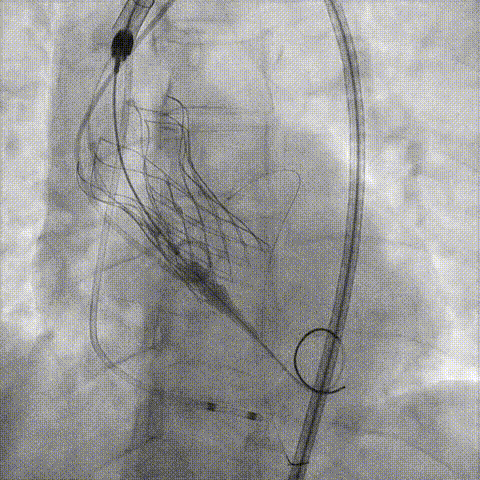

预置Telescope™导引延长导管及导丝保护左冠,

18mm球囊预扩张再次评估冠脉闭塞风险。

介入经过及结果

Telescope™+Runthrough

18mm*40mm 预扩张

预埋 Resolute Integrity 3.5*26mm

再次评估左冠开口

第一次释放